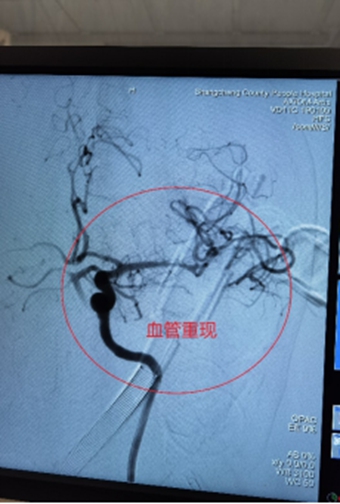

6月7日下午,家住长竹园乡的刘先生突然出现左侧肢体无力,双眼向右侧斜视(凝视),言语不清、口角歪斜等症状,下午3点家属将其送入我院,急诊行头颅CT未见出血,但其右侧颈内动脉末端及大脑中动脉可见高密度征,考虑为大血管病变所致的急性脑梗死,NIHSS评分:14分,mRS评分4分,因无溶栓禁忌,与家属沟通后给予急诊静脉溶栓(阿替普酶,0.9mg/Kg体重)治疗。溶栓大约10分钟左右患者开始出现烦躁,头痛,(NIHSS评分:14分,mRS评分5分)急诊头颅CT未见出血转化,在右侧大脑中动脉供血区出现大片状低密度灶,情况变得更加凶险,卒中团队综合考量认为患者此时急需血管开通治疗以避免脑细胞进一步坏死,再次与患者家属沟通病情后开始急诊取栓治疗。下午3点30分患者被紧急推入介入手术室。

在卒中中心团队的默契配合下,手术顺利取出血栓,实现左侧大脑中动脉完全再通。从动脉穿刺成功到血管完全再通历时仅40分钟。术后患者生命体征平稳,术后1周,患者病情稳定,神志清楚,对话流利,凝视症状缓解,NIHSS评分由14分变为8分。